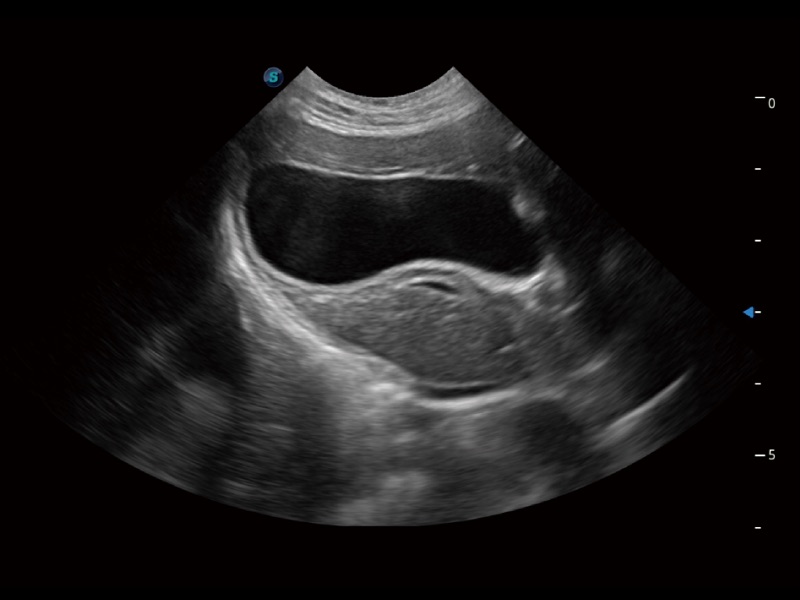

优异的基础图像

ProPet 70 全新的动物超声智能软件和丰富的探头群,为动物医生提供了高清晰度和精细分辨率的图像,无论在宠物、马科、畜牧还是实验室动物等应用中都可以轻松应对,为您的日常工作带来满意的体验。

• Auto Bladder 膀胱自动测量

一键自动识别膀胱壁及自动测量膀胱容积,不受膀胱形状和大小的限制,帮助医生快速精准获得测量的数据。

(猫)胆囊